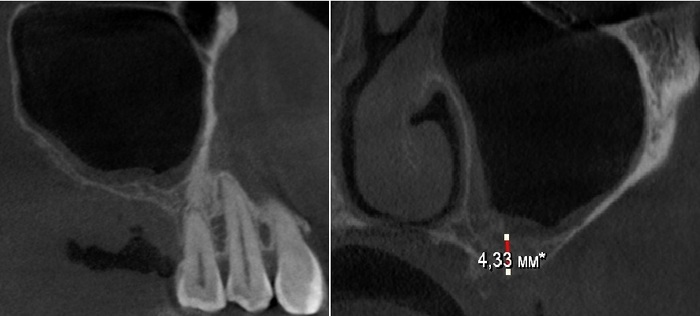

Фрагмент компьютерной томографии (вид сбоку):

Первый вопрос, который я задал, – почему не было проведено исправление прикуса до имплантации?

Пациентка сказала, что обсуждала этот вопрос, но финансово она не тянула.